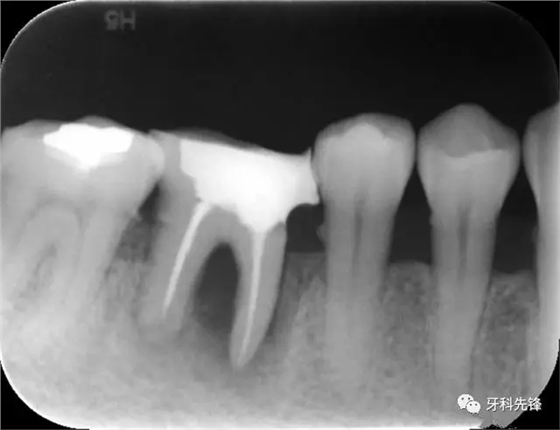

圖1術(shù)前X光片

640.webp.jpg

640.webp (1).jpg